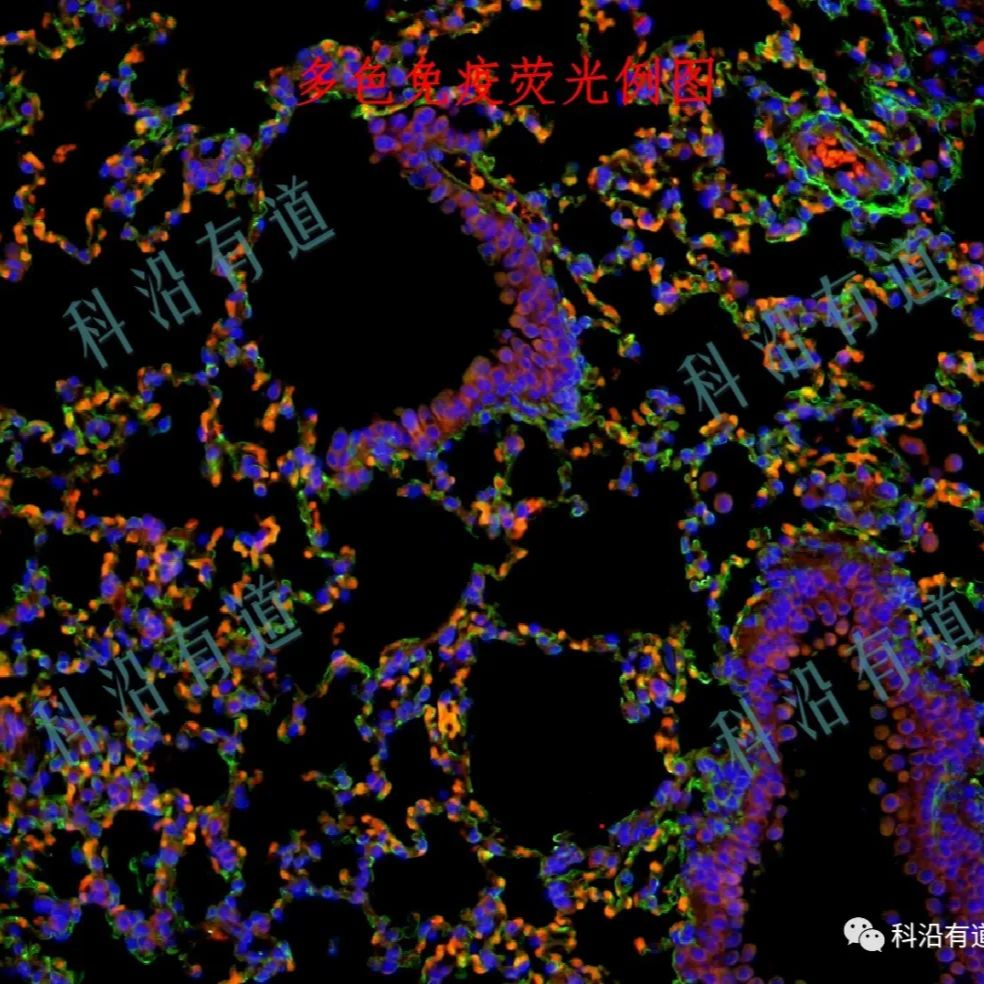

多重免疫荧光(TSA)服务